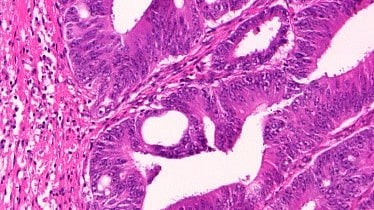

Completed genetic testing would determine whether a patient had Lynch syndrome (LS), a hereditary marker for a higher-than-average predisposition for developing colorectal cancer as well as other cancers including endometrial and ovarian. Early identification of LS in a patient’s family members has the potential to reduce their cancer risk and mortality, increasing the medical benefit and thereby ultimately lowering testing costs, the study found.